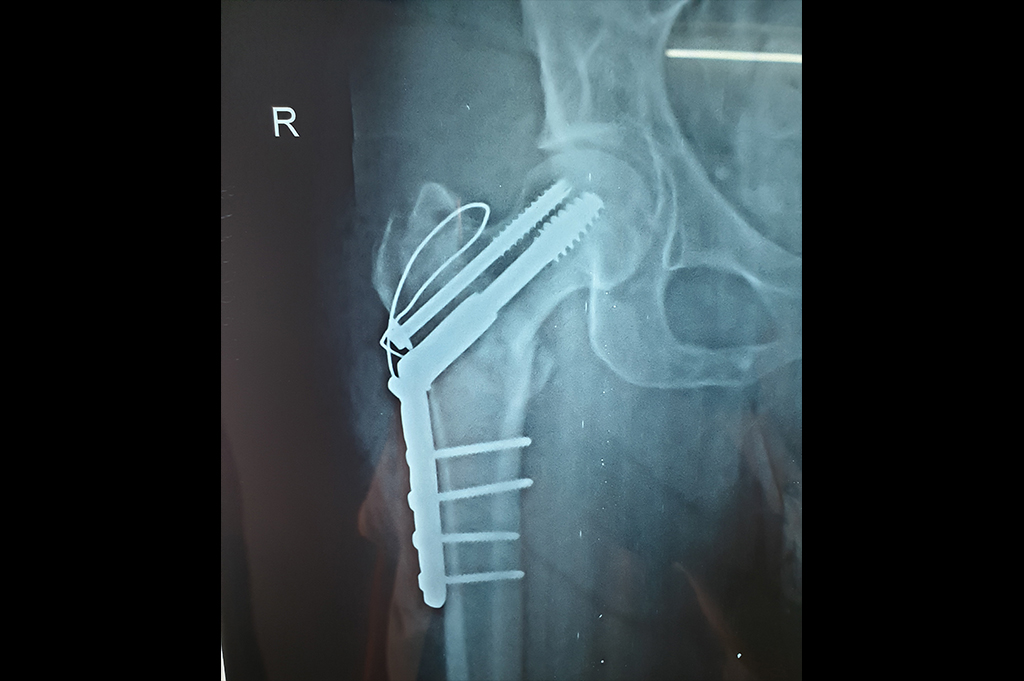

Periprosthetic Fracture THR